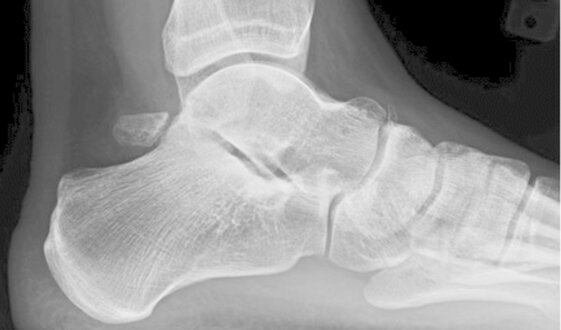

Os Trigonum

- Embriologicamente il corpo dell’astragalo e il suo processo posteriore sono centri di ossificazione differenti. Tra il settimo e il tredicesimo anno di vita è visibile un nucleo di accrescimento osseo, l’ Os Trigonum, che normalmente si fonde con il processo posteriore dell’astragalo entro un anno dalla sua comparsa radiografica. Se questo processo non avviene il corpo dell’astragalo rimarrà separato dall’os trigonum anche in età adulta diventando così un osso accessorio a volte doloroso. Circa 7 persone su 100 hanno l’os trigonum. Di solito l’osso è presente bilateralmente e ha forma triangolare e non supera 1cm di grandezza. Il tendine del flessore lungo dell’alluce è situato appena mediamente all’os trigonum e questo rapporto anatomico è causa della sindrome dell’impingement posteriore di caviglia (PAI), una tipica patologia dei ballerini (soprattutto di danza classica) e di chi in generale ripetutamente effettua una flessione plantare della caviglia causando un effetto “schiaccianoci” sulla caviglia posteriore che si infiamma cronicamente causando dolore ed impotenza funzionale e gonfiore posteriore associato che riduce ulteriormente la capacità di plantarflettere il collo-piede riducendo la performance dell’atleta o del ballerino.

Clinicamente i sintomi principali sono il dolore nella regione posteriore della caviglia ed il gonfiore associato che causano un’impotenza funzionale. La sintomatologia a volte può essere importante con un esercito acuto, in questi casi avviene una vera e propria frattura dell’os trigonum che si distacca dal corpo astragalico.

La diagnosi viene posta con una visita accurata e l’ausilio di una radiografia in laterale sotto carico e di una RMN ad alta risoluzione.

Il trattamento può essere conservativo o chirurgico. Inizialmente ci si avvale di terapie fisiche e crioterapia locale per il controllo del dolore e dell’infiammazione. L’eventuale trattamento chirurgico consiste nell’asportazione dell’os trigonum per via artroscopica con accesso posteriore. L’intervento è poco invasivo, in day-hospital, l’anestesia è loco-regionale, la ripresa è rapida e con buoni risultati clinici e funzionali seguendo un adeguato protocollo riabilitativo.

A sinistra esempio di immagine radiografica e a destra di immagine RMN che evidenziano voluminosi Os Trigonum che dovranno essere asportati per via artroscopica con accesso posteriore come nella foto sotto.